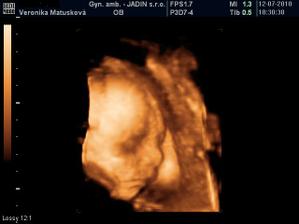

Adamko - 3D/4D

No tot vidno, že je náš syn, sa hanbil a hanbil až sa ukazovať nechcel....ale niekedy sa to podarilo, aj ked to nie je nejaká sláva. Pán doktor nám potvrdil chlapčeka, tak sme radi, vajká ukazoval ako len vedel len toho pipíka stále schovával. Ale je to za nami, pán doktor nás pekne popísal čo je kde, poodmeral nás a povedal, že je všetko v poriadku.